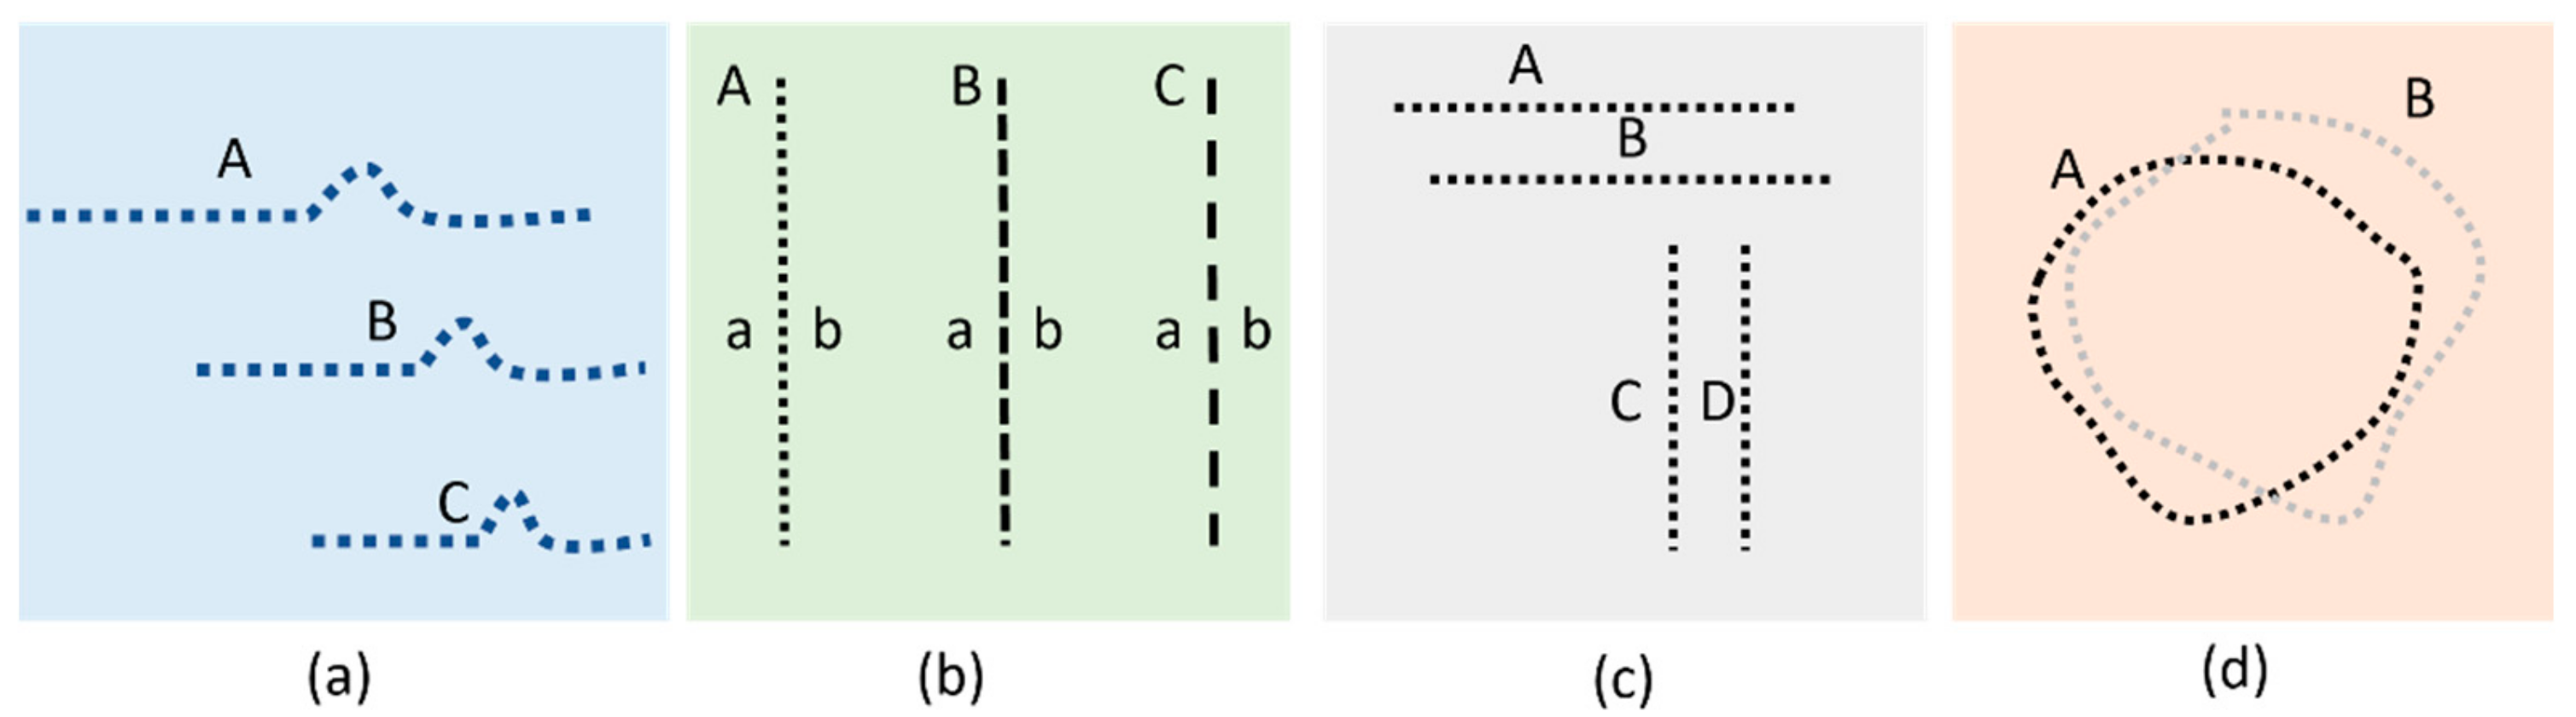

3.1. Effect of CSR in the Visual Field

3.2. Spherical Shape CSR Modeling